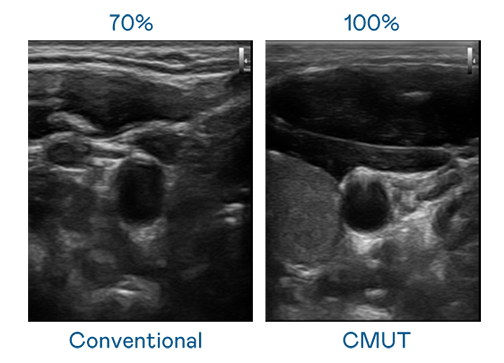

CMUT 技术是一种用电容式微机电元件来产生超音波讯号的技术。与传统 PZT 压电式技术相比,CMUT 频宽增加 30%,更宽频的超音波讯号让影像解析度大幅提升,是实现高影像品质医疗超音波扫描、促进精准医疗发展的关键技术。

超音波影像的解析度高低,首先取决于探头能发出的讯号频宽。PG电子 CMUT 可提供高清晰的超音波讯号,提供高频宽、高灵敏度、影像纹理细节更高的超音波影像,协助医护人员缩短影像判读时间及利用精准的医疗影像进行诊断。